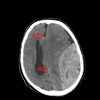

How well did you know this?

1